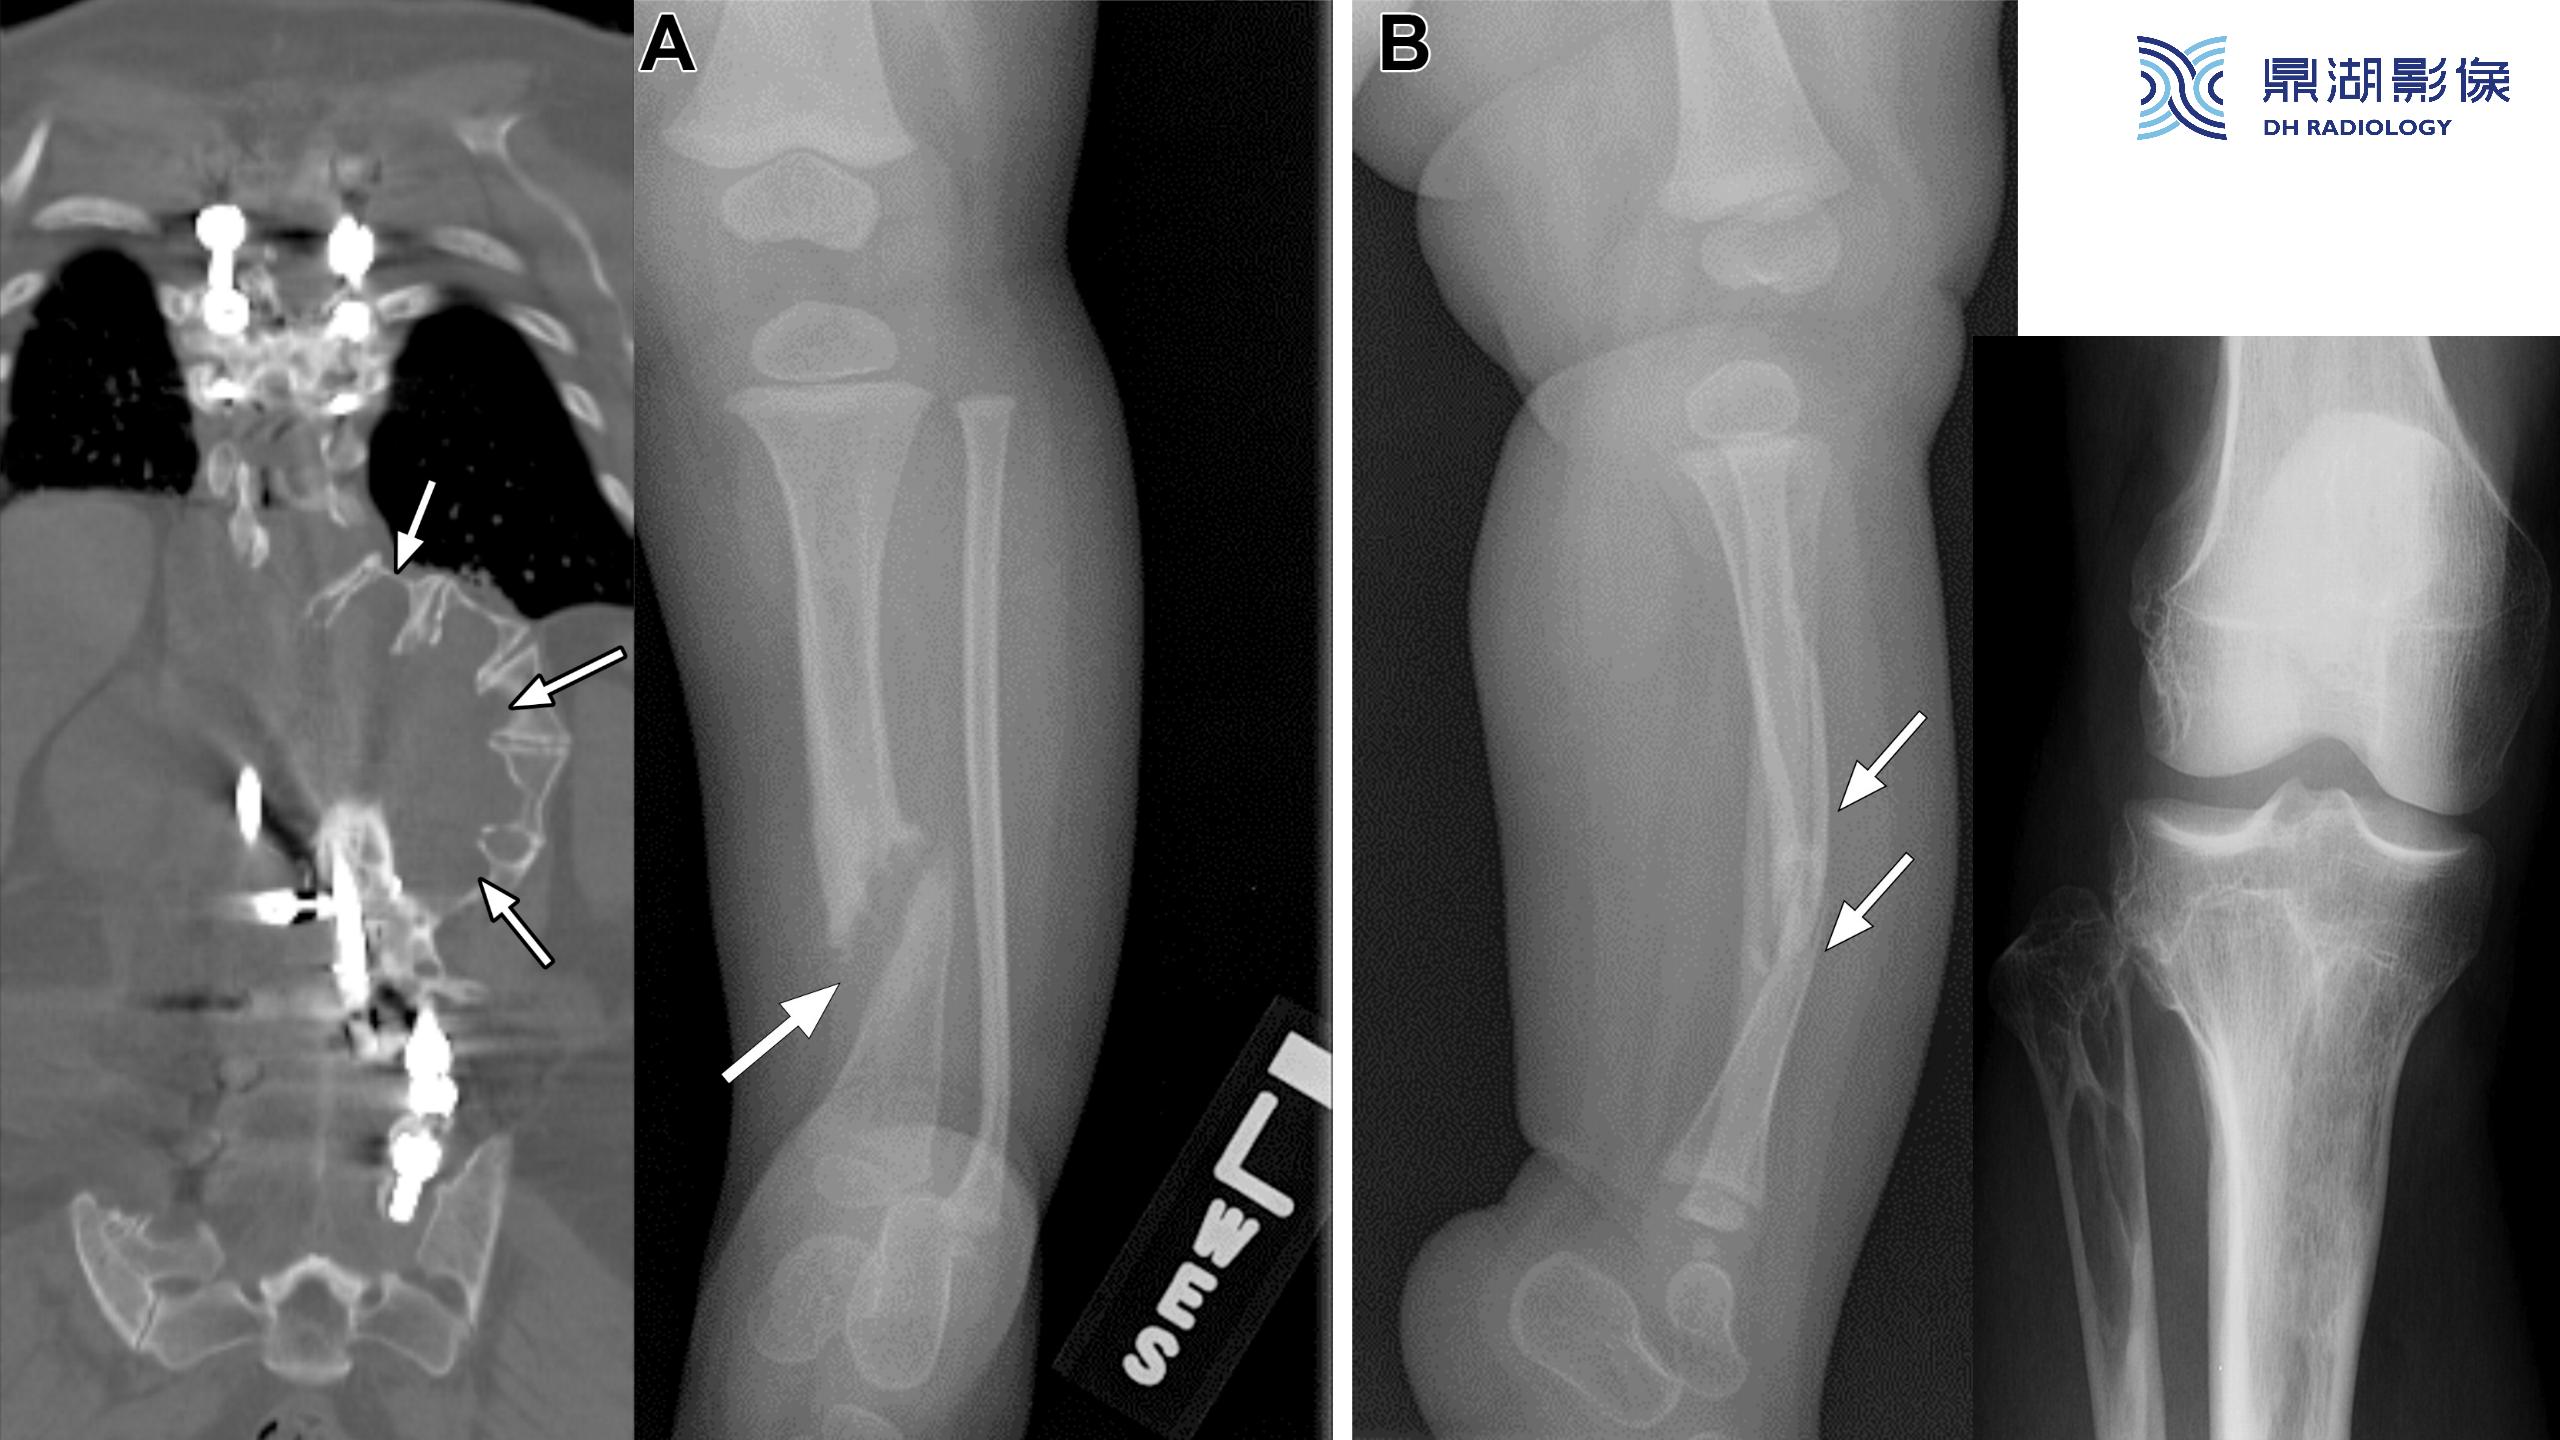

神经纤维瘤病(NF1)